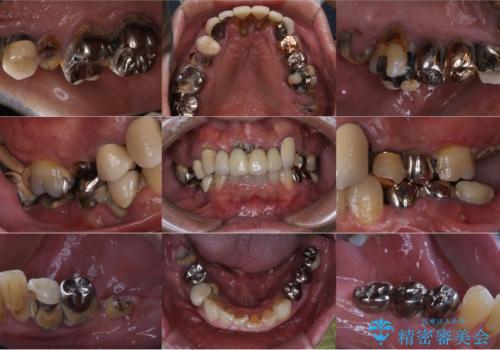

孫から口臭を指摘され来院、全顎治療で噛み合わせ、見た目、口臭全て劇的改善!

- お孫さんに口臭を指摘されたことで治療を決断し、来院されました。

歯周病、虫歯、合わない被せ物がニオイの原因となっていたため、そのすべてを治療することになりました。

まずは歯周病の治療と抜くしかない歯を抜き、インプラント治療とセラミック治療を行いました。

治療中でも見た目が問題ない様に仮歯を製作していきますが、今回は奥歯に仮歯を入れることが不可能であったため、インプラントが使用できるまでの半年間は入れ歯を使用して頂きました。